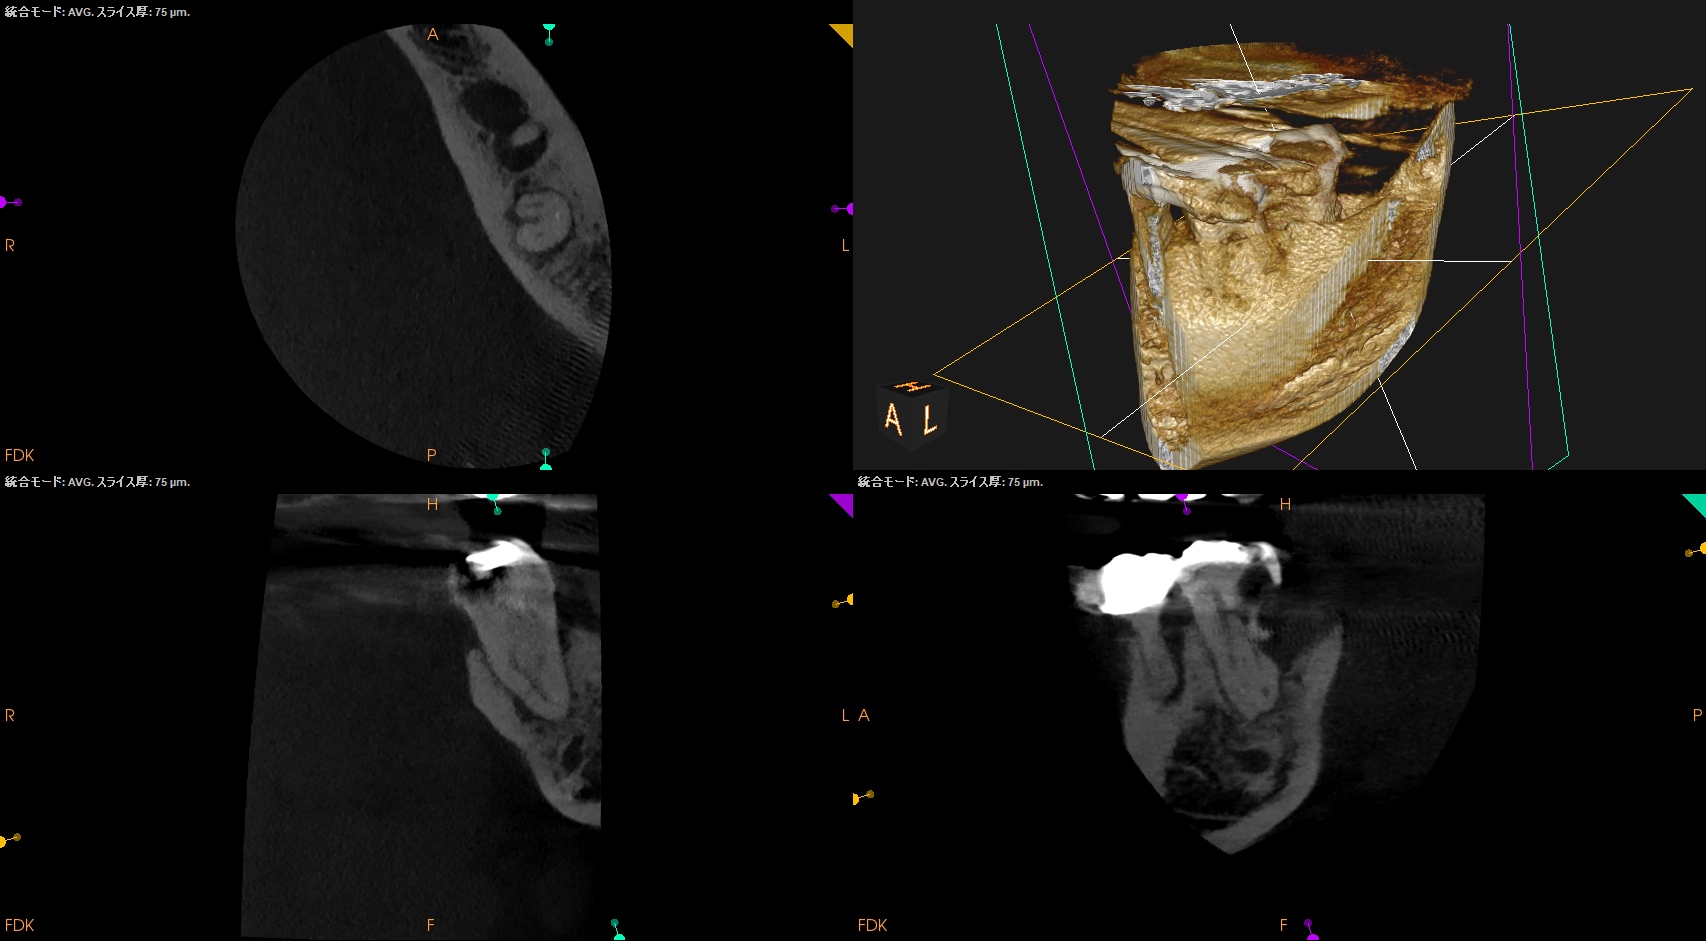

CBCT(2025.12.10)

ML

MB

D

遠心方向から見ると、

絶望的な状態であることがわかる。